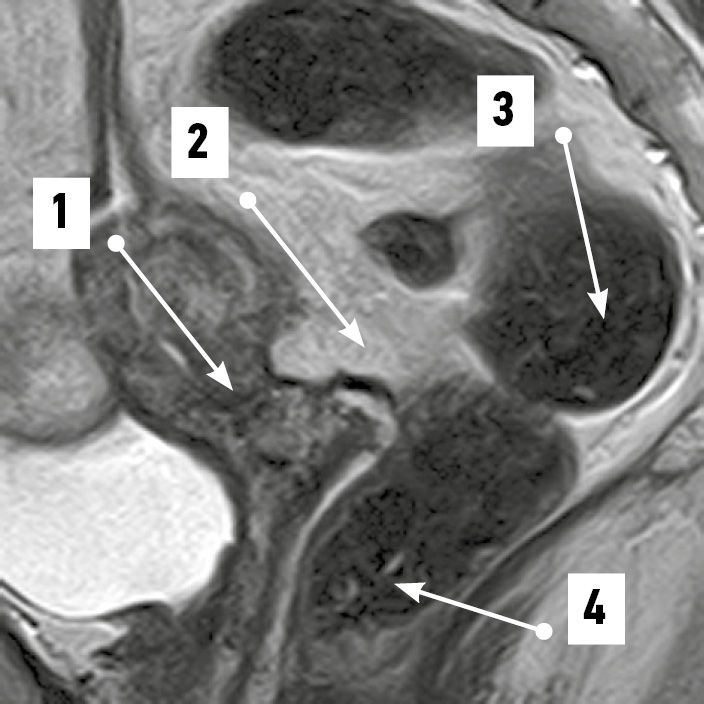

Рис. 3. Приближенные матка и надвлагалищный участок прямой кишки. Магнитно-резонансная томограмма органов таза в режиме SG T2: 1 — матка; 2 — надвлагалищный участок прямой кишки, извит во фронтальной плоскости, прилежит к матке; 3 — влагалищный участок прямой кишки. / Fig. 3. Approximate uterus and supravaginal segment of the rectum. SG T2-magnetic resonance imaging of the pelvic organs: 1 — uterus; 2 — supravaginal segment of the rectum, which is convoluted in the frontal plane, adjacent to the uterus; 3 — vaginal segment of the rectum.

По результатам МРТ-анализа при положениях матки anteversio-anteflexio надвлагалищный участок прямой кишки в половине случаев (52,4%) был извит во фронтальной плоскости (рис. 1). В 38,1% случаев кишка имела ход, соответствующий вогнутости крестца (рис. 2), ещё в 9,5% сагиттальный изгиб кишки был значительно выражен. Расстояние между маткой и прямой кишкой в надвлагалищном участке в среднем составило 5,93±0,97 мм. Здесь прослеживался значительный разброс минимальных и максимальных величин, свидетельствовавший о разнообразии положения органов: от их крайней степени близости — 0,00 мм (рис. 3) до удалённого положения — 17,00 мм (рис. 4). Последнее может служить анатомической предпосылкой для положения петель тонкой кишки в относительно широком прямокишечно-маточном углублении.